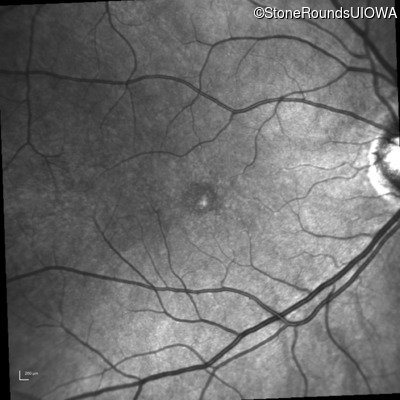

Fluorescein Angiography - Right - 20/20 -1

Exemplar